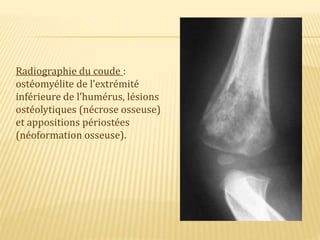

Radiographie du coude :

ostéomyélite de l’extrémité

inférieure de l’humérus, lésions

ostéolytiques (nécrose osseuse)

et appositions périostées

(néoformation osseuse).

Radiographie du coude: ostéomyélite de l’extrémité inférieure de l’humérus, lésions ostéolytiques (nécrose osseuse) et appositions périostées (néoformation osseuse).